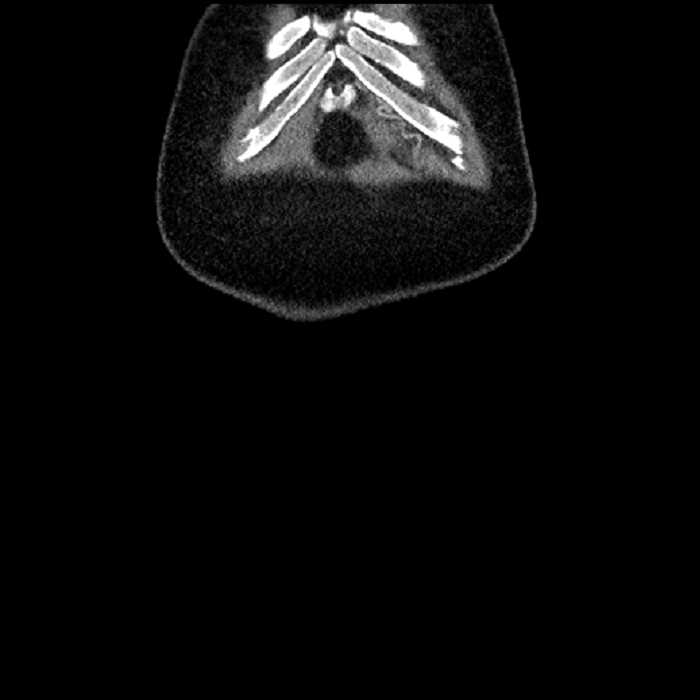

Age: 63

Sex: Male

Indication: Abdominal pain

• Large fluid density structure in hepatic segments 7 and 8 measuring 10 x 7 x 7 cm with internal septation and circumferential ill-defined low density compatible with edema

• Peripherally enhancing subcapsular collections along the anterior margin of the left hepatic lobe measuring 3 x 1 cm and 2 x 1 cm

• Hepatic abscess

Acute sigmoid diverticulitis complicated by a small contained perforation and a large abscess in the right hepatic lobe. Additional small subcapsular abscesses along the anterior margin of the left hepatic lobe.

• The classic CT imaging appearance is a double target sign with internal low density surrounded by an internal enhancing rim (capsule) and a low density external rim (edema)

Hepatic abscess showing the double target sign with low density internally surrounded by a thin inner enhancing rim (red arrow) and ill-defined outer low density rim (yellow arrow). Blue arrow indicates an internal septation. Red arrows: additional smaller subcapsular abscesses. Red arrow: focal contained perforation associated with diverticulitis.